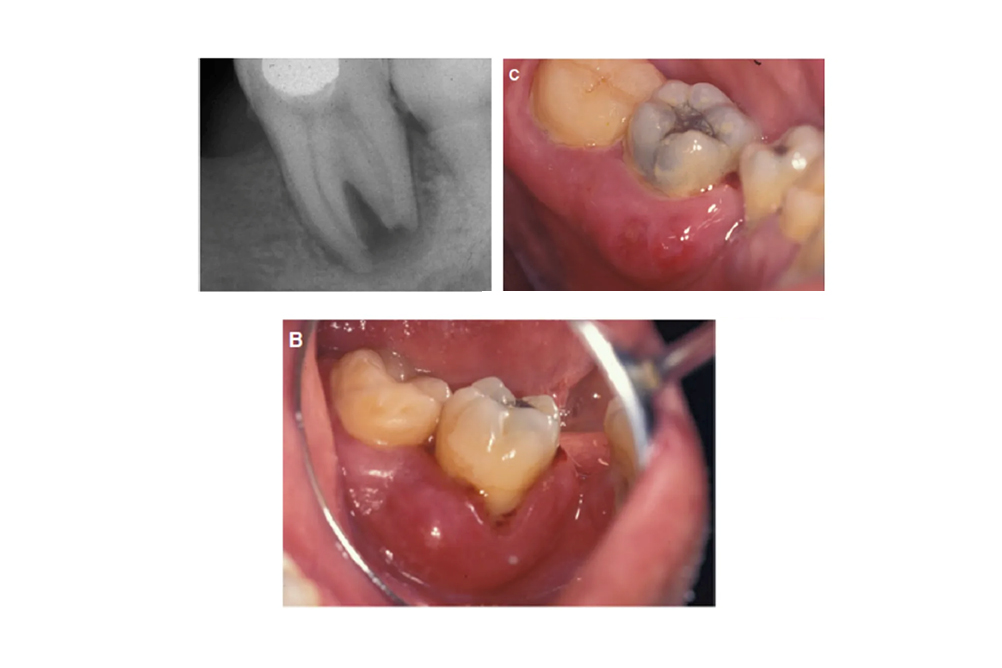

牙根上的菌相失衡,其生物膜中會有較高的牙周致病菌,進而引起周圍牙齦及齒槽骨長期的慢性發炎。當破骨細胞及蛋白水解酶因此活化時,會引起牙周組織的破壞,進而導致牙齒有搖動度上升的臨床症狀。

所以當您的牙齦處於長期的發炎腫脹時,這可能會有利於牙周致病菌的生長。當牙齒過於搖動被拔除的時候,大部分牙根上的細菌可能會脫離牙齦及齒槽骨而促進其發炎的緩解。慢性牙周病發炎的過程不見得會有疼痛的現象,部分的病患可能只覺得牙齦有腫脹的感覺。

當您覺得牙周病會痛時,有部分的案例可能會看到牙齦膿腫甚至是蜂窩性組織炎臉腫起來的症狀。這時候牙齦或周圍的齒槽骨會呈現高度感染的現象。